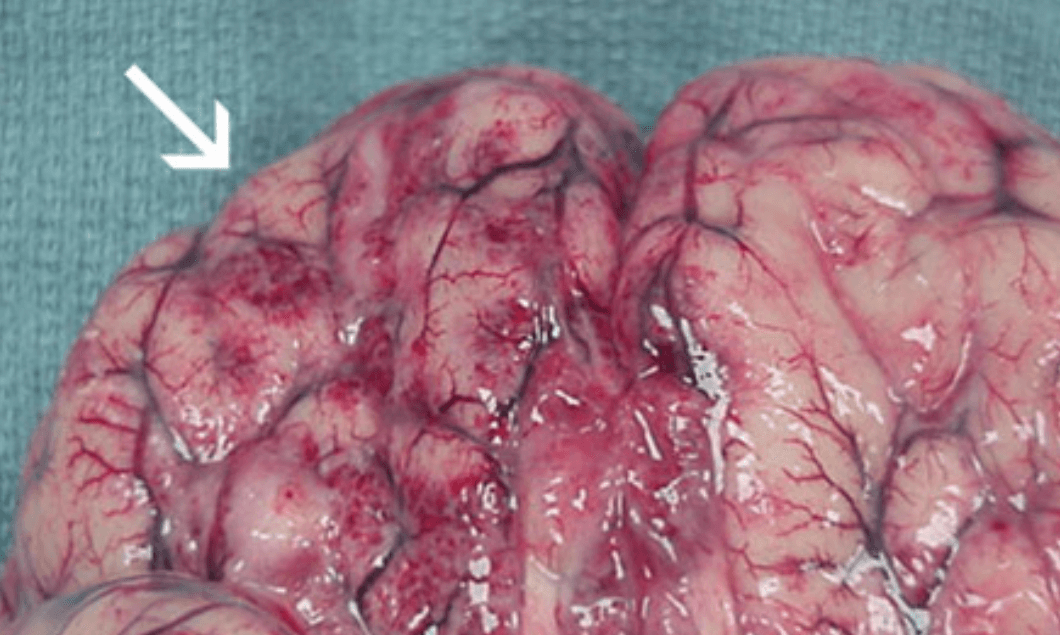

네글레리아 파울러리는 물속에서 사람의 코를 통해 뇌에 침투하면 세포를 파괴하고 심각한 피해를 초래합니다. 1962년부터 2020년까지 확인된 환자 중 151명 가운데 147명이 사망(치사율 97.3%)한 것으로 알려져 있습니다. 이에 따라 보건 당국은 예방을 위해 물 속에서의 안전한 행동과 적절한 위생 수칙을 주의하도록 당부하고 있습니다.

지난 해, 국내에서 처음으로 파울러자유아메바(네글레리아 파울러리)에 감염된 환자가 발생하여 사망했습니다. 해당 환자는 태국에서 4개월간 체류한 후 국내에 들어온 50대 남성으로, 귀국 당일 발열 등의 증상이 나타나고 다음날 뇌수막염 증상으로 응급실에 이송되어 치료를 받았으나 21일에 숨졌습니다. 이로써 국내 최초의 파울러자유아메바 감염 사례가 발생하였습니다. 파울러자유아메바는 뇌수막염을 일으켜 중증일 경우 사망에 이를 수 있는 원충입니다. 주로 호수나 강에서 수영이나 레저 활동을 할 때, 코를 통해 뇌로 침입하여 감염됩니다. 비염 치료를 위한 코세척기를 통해도 감염될 수 있습니다. 전 세계적으로 감염 사례는 드물지만, 감염 후 증상 진행이 빠르고 치명적입니다. 감염되면 2~3일 동안 잠복기를 거친 후 7~15일 동안 증상이 나타나며, 초기에는 두통과 혼미 상태를 보이다가 심한 두통, 발열, 구토, 혼수 상태로 이어져 사망에 이를 수 있습니다. 국내에서는 2017년에 전국 상수원 조사 결과 52개 지점 중 6개의 지점에서 파울러자유아메바 유전자가 검출되어 존재 가능성이 보고된 적이 있지만, 이번이 처음으로 국내에서 감염 환자가 발생하였습니다. 미국, 파키스탄, 인도, 중국, 일본 등에서도 감염 사례가 보고되었습니다. 해당 환자가 체류했던 태국에서는 지난해를 포함하여 40년간 외국인 여행자 17명이 파울러자유아메바에 감염된 사례가 있었습니다. 질병관리청장은 여행할 때 해당 지역의 수영 및 레저 활동을 삼가고 깨끗한 물을 사용하는 등 각별히 주의해야 함을 당부하였습니다.